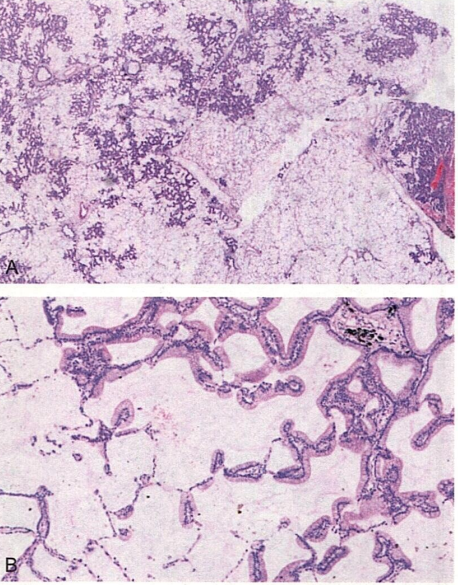

患者女,55岁。咳嗽、咳痰带血。X线显示右下肺野多灶性阴影。镜下改变如图所示。

1.在遗传学方面,与该病理学类型关系密切的突变基因是